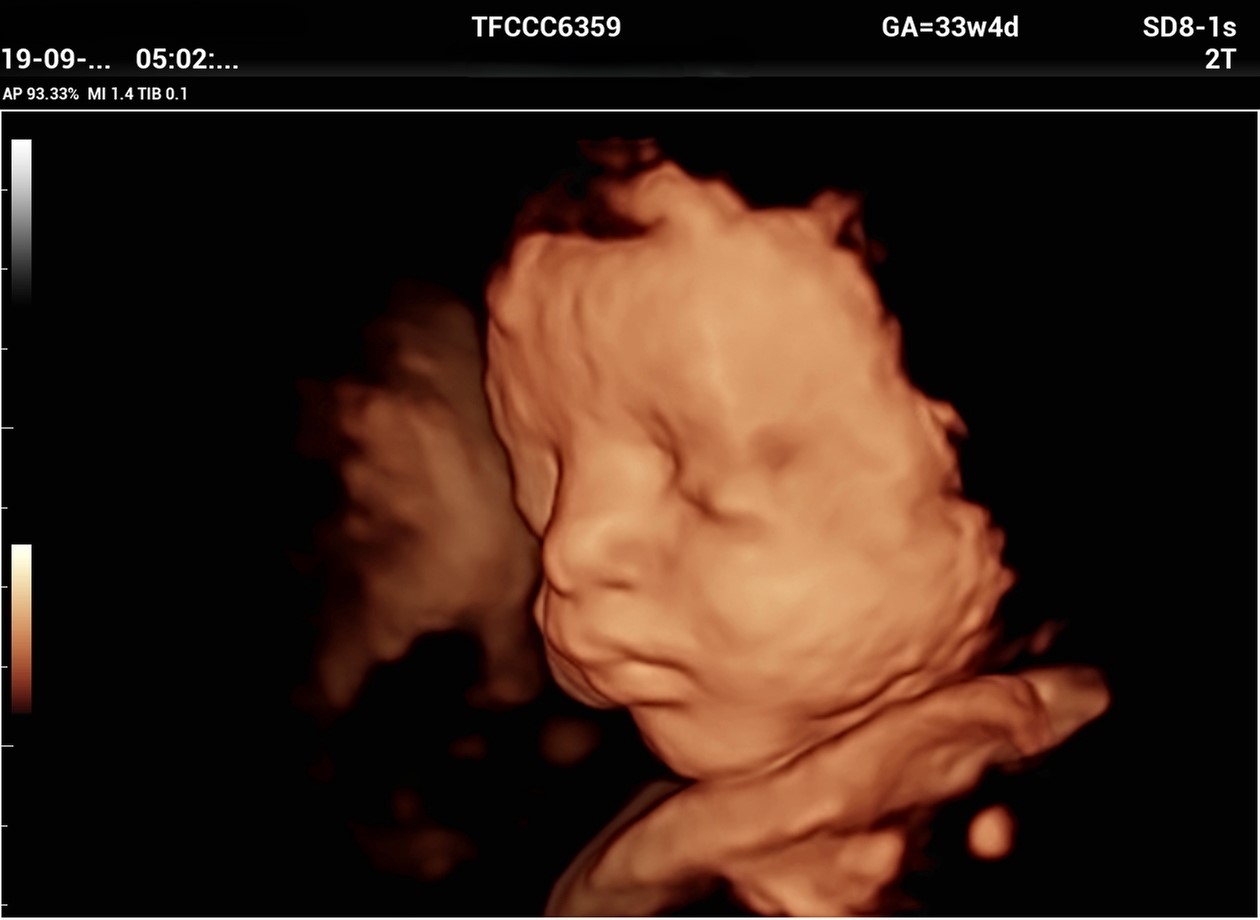

3rd Trimester & Multifetal Pregnancy

• Interval growth assessment